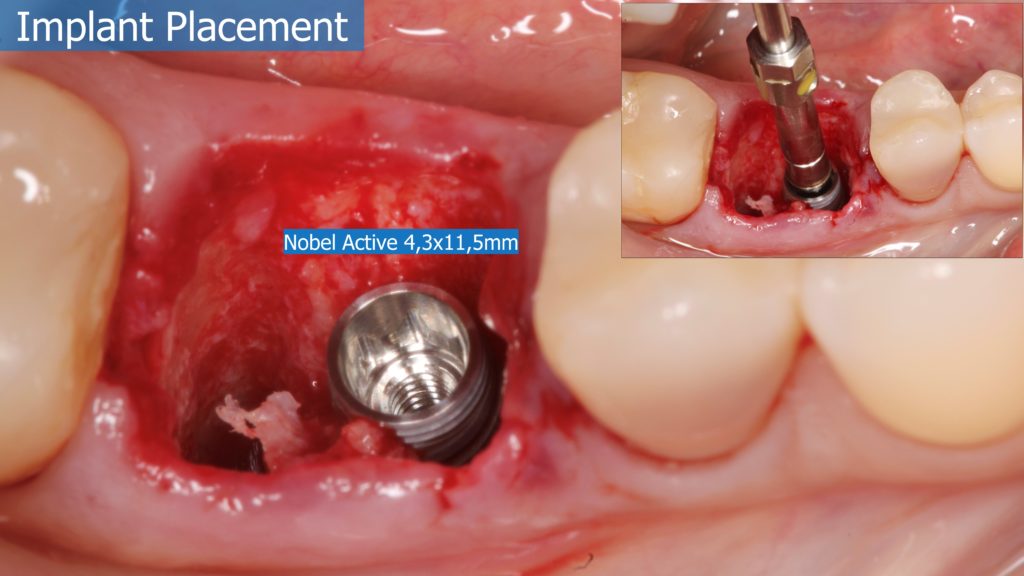

6-12 Months, Augma Bone Cement Academy, Bone Cement Expert, Clinical Cases, Clinical Indication, Clinician, Collagen Sponge/Plug, Coverage Used, Dental Notation, Images, Immediate Placement, Lower Left Molar, Media, Post-Op Period, Socket Grafting, Wound Dressing

Immediate Posterior Implant with Bone Graft

A healthy 36 year old woman comes to the clinic with pain and swelling in the area of the inferior left molars. In the intraoral observation, a vestibular fistula was identified, and the complementary exams confirmed a bone lesion caused by a root perforation (poorly executed false post) on the first lower left molar #36 (19). It was decided to do antibiotic therapy for a week and then the tooth extraction with immediate implant placement and bone graft. 4 months post-op the definitive zirconia/ceramic crown would be was made.